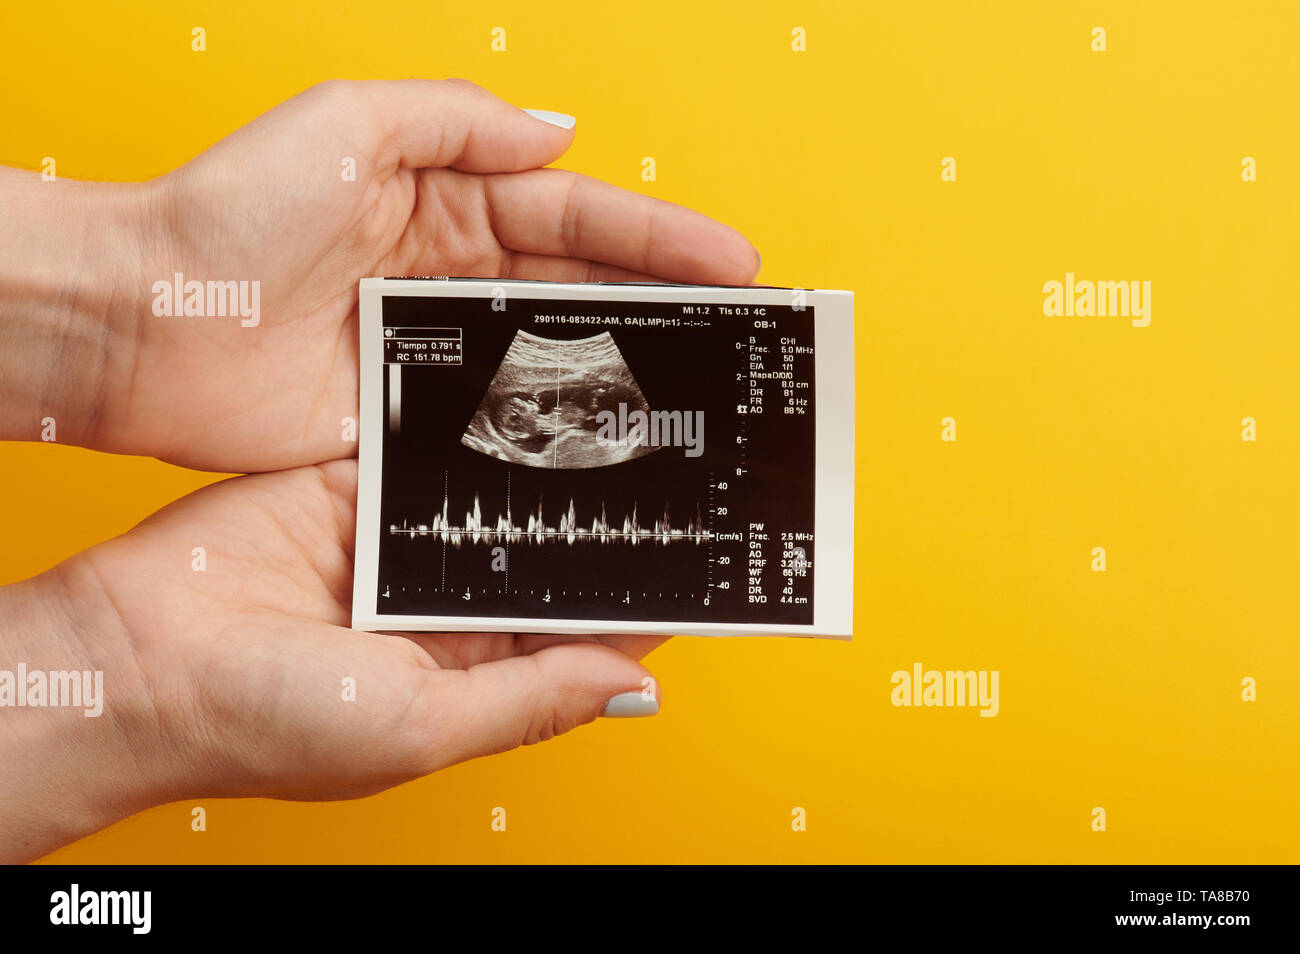

Ultrasound scan of future baby with heart beat parameters Stock Photohttps://www.alamy.com/image-license-details/?v=1https://www.alamy.com/ultrasound-scan-of-future-baby-with-heart-beat-parameters-image247276010.html

Ultrasound scan of future baby with heart beat parameters Stock Photohttps://www.alamy.com/image-license-details/?v=1https://www.alamy.com/ultrasound-scan-of-future-baby-with-heart-beat-parameters-image247276010.htmlRFTA8B22–Ultrasound scan of future baby with heart beat parameters

Hand hold ultrasound scan with heart beat of newborn baby Stock Photohttps://www.alamy.com/image-license-details/?v=1https://www.alamy.com/hand-hold-ultrasound-scan-with-heart-beat-of-newborn-baby-image247276078.html

Hand hold ultrasound scan with heart beat of newborn baby Stock Photohttps://www.alamy.com/image-license-details/?v=1https://www.alamy.com/hand-hold-ultrasound-scan-with-heart-beat-of-newborn-baby-image247276078.htmlRFTA8B4E–Hand hold ultrasound scan with heart beat of newborn baby

Ultrasound scan with future baby parameters in hand on yellow background Stock Photohttps://www.alamy.com/image-license-details/?v=1https://www.alamy.com/ultrasound-scan-with-future-baby-parameters-in-hand-on-yellow-background-image247276065.html

Ultrasound scan with future baby parameters in hand on yellow background Stock Photohttps://www.alamy.com/image-license-details/?v=1https://www.alamy.com/ultrasound-scan-with-future-baby-parameters-in-hand-on-yellow-background-image247276065.htmlRFTA8B41–Ultrasound scan with future baby parameters in hand on yellow background